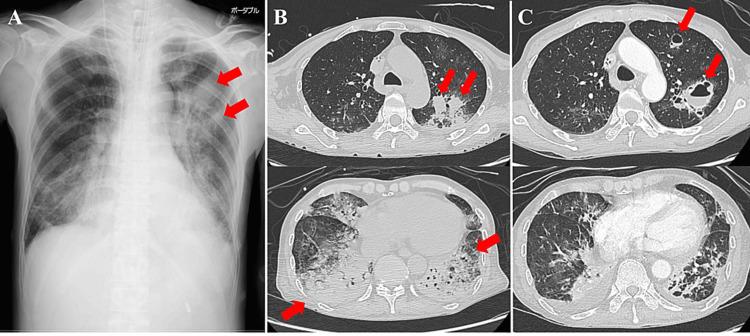

We report two patients who were treated with remdesivir, steroids, and tocilizumab for severe coronavirus disease 2019 (COVID-19) and developed lung abscesses and pleuritis. Although complications due to bacterial infections are often reported in COVID-19 patients, these severe infections are rare. Patients receiving tocilizumab are at a high risk of developing serious bacterial infections, and the diagnosis is often delayed because symptoms such as fever and elevated C-reactive protein levels are often minimal. The possibility of complications owing to severe bacterial infections should be considered when treating patients with severe COVID-19.

我们报告了两名接受瑞德西韦、类固醇和托珠单抗治疗的重症2019冠状病毒病(COVID-19)患者,他们出现了肺脓肿和胸膜炎。虽然COVID-19患者中常报告有细菌感染引起的并发症,但这些严重感染很少见。接受托珠单抗治疗的患者发生严重细菌感染的风险很高,而且由于发热和C反应蛋白水平升高等症状通常很轻微,诊断往往会延迟。在治疗重症COVID-19患者时,应考虑到严重细菌感染导致并发症的可能性。